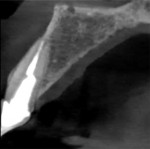

An 84-year-old male patient presented to the practice for an emergency appointment. He stated that a crown on one of his upper front teeth had come off and needed to be recemented. The patient's records indicated that the tooth (No. 7) had been endodontically treated and restored with a fiber post, core buildup, and crown more than 5 years prior to his current presentation. During the clinical examination, it was noted that the tooth had fractured supragingivally, leaving the core and a portion of the fiber post in the detached crown (Figure 1). A periapical radiograph was taken to assess the remaining root structure (Figure 2). Structurally, the tooth was deemed non-restorable, and treatment options were discussed with the patient, including replacement with an implant-supported crown.